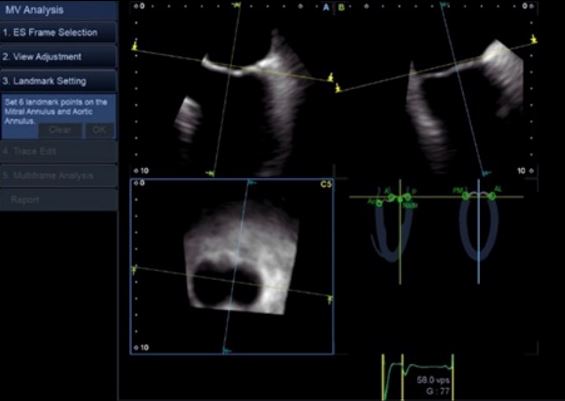

Аналіз мітрального клапана в 4D (4D MVA)

Цей унікальний інструмент забезпечує анатомічну та функціональну оцінку мітрального клапана, проводячи близько 40 вимірювань за 30 секунд, та допомогає лікарю при плануванні інтервенційного втручання, наприклад для операції транскатетерної імплантації мітрального клапана.

Діагностика виконується за допомогою трансезофагеального 4D датчика PEI-512VX.

- Інтуїтивно-зрозумілий кольоровий 3D аналіз

- Функціональна оцінка мітрального клапана

- 4-віконний дисплей (обрані користувачем зрізи, різні площини сканування, 3D-реконструкція)

- Автоматизовані вимірювання мітрального клапана з виведенням в реальному часі більш ніж 40 показників

- Реконструкція мітрального клапана візуалізує форму стулок клапана, що допомагає оцінити пролапс або деформацію.